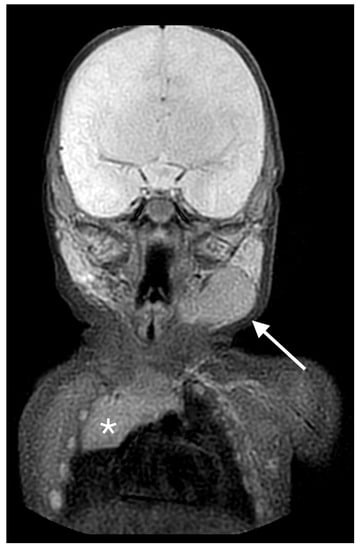

A 11-month-old toddler was referred to our Pediatric Emergency Unit for a one-week history of rhinitis and two episodes of vomiting. His prior clinical history was unremarkable. On clinical examination an acute upper respiratory infection was diagnosed, with palpable reactive bilateral cervical lymph nodes. During clinical examination a swelling located on the left submandibular area was found and an enlargement of the left submandibular gland was suspected. The swelling was painless, soft, non-pulsatile and non-fluctuating without any signs of inflammation. Blood tests were normal, showing no increase of inflammatory markers nor immunological abnormalities. A soft-tissue ultrasound of the mass was performed, showing an enlargement of the left submandibular gland, reactive lymph nodes in the left cervical area and into the parotid parenchyma, and a 3.5 × 1.7 cm hypoechoic irregular lesion, with intralesional vascular signs and punctate and linear echogenic foci resulting in a “speckled” or “salt and pepper” pattern (Figure 4a).

Ectopic cervical thymus in a 11-month-old toddler accidentally noticed on clinical examination for an acute upper respiratory infection. (a) Longitudinal sonogram showing a 3.5 × 1.7 cm hypoechoic lesion (white arrow), with intralesional vascular signs and punctate and linear echogenic foci resulting in a “speckled” or “salt and pepper” pattern, compatible with ectopic cervical thymus. (b) Portion of thymic tissue (white arrow) extending into deeper layers, likely connecting the ectopic mass to the orthotopic thymus.

The echo pattern of this mass was identical to that of the normal thymus located in the superior mediastinum, thus the diagnosis of ECT was suggested. Additionally, the ultrasound showed a portion of thymic tissue extending into deeper layers, a probable remnant of its migration during embryogenesis, aiding in its identification (Figure 4b).